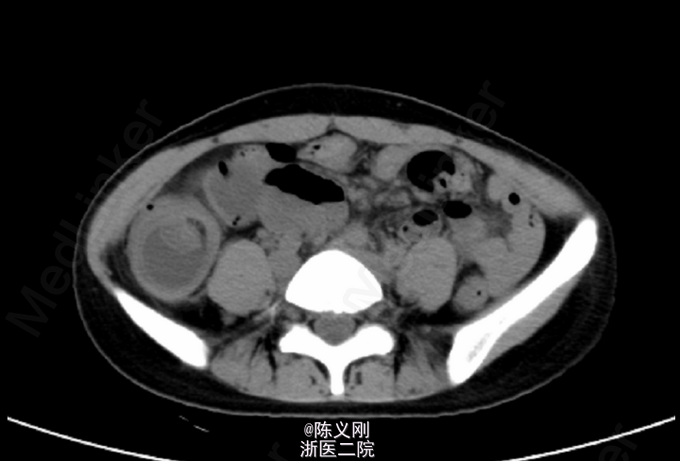

查体:中下腹压痛,右侧为主,无反跳痛,无肌紧张; 腹部平片:右下腹部升结肠、回盲部及部分小肠肠壁明显增厚、水肿,考虑炎症可能大,局部肠管套叠待排。 腹部CT:右下腹部升结肠、回盲部及部分小肠肠壁明显增厚、水肿,局部一段见靶环征。

诊断:肠套叠。 处理:急诊行“肠套叠复位+畸形小肠切除+肠重排+肠固定”,术中见:距回盲部可见长约80cm回肠套入升结肠,近端回肠肠管充血、水肿并扩张,余肠管未见明显穿孔、肿瘤及梗阻。将回肠手法复位后,可见距回盲部约70cm处一长约8cm垂直于回肠的畸形小肠,予以切割闭合器离断畸形小肠,于距回盲部取回肠及升结肠各10cm并排缝合固定。 术后予百定5.0g静滴bid抗感染,余吸氧、心电监护、护胃、化痰、补液等对症支持治疗。注意监测生命体征及腹腔引流情况。